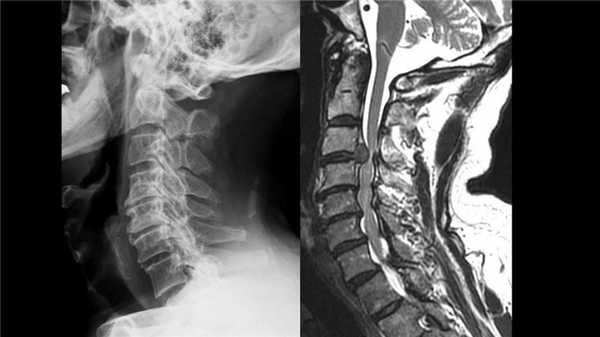

Стеноз шейного отдела вследствие грыжевого выпячивания.

Грыжа и клювовидные остеофиты, слева рентген, справа МРТ.